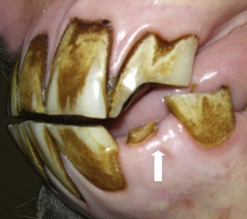

Fig. 8.11 A marked (circa 5 cm long) overgrowth is present on this caudally situated supernumerary mandibular CT (412) that has caused marked ulceration of the adjacent cheeks (arrow).